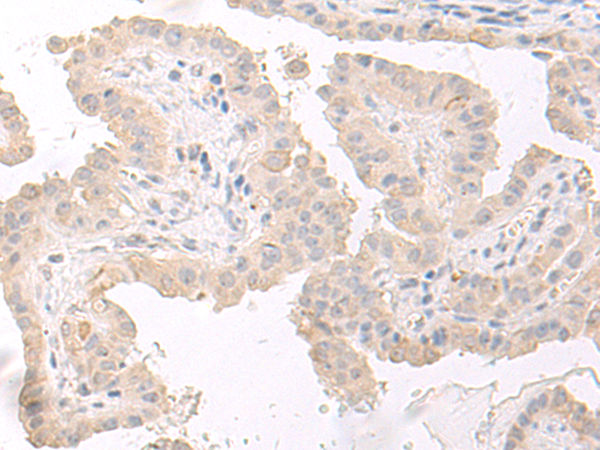

分类: 科研抗体货号: P02834别名: S11应用: WB,IHC反应种属: Human, Mouse, Rat